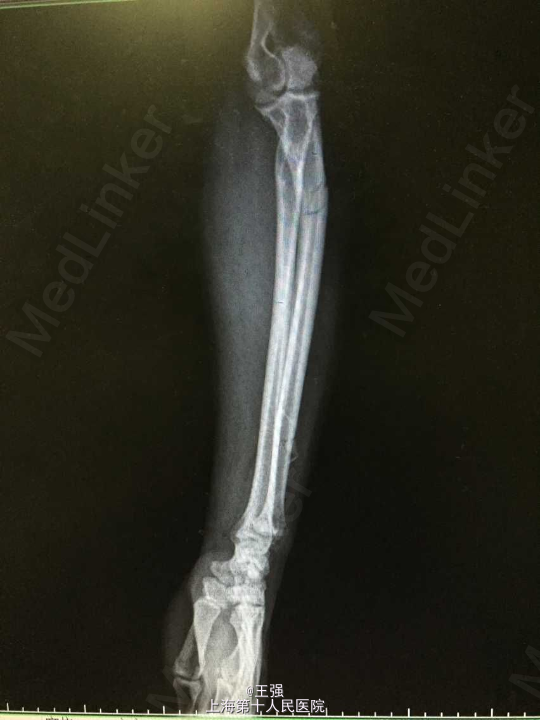

患者男,72岁 主述:左前臂外伤后肿痛、畸形、活动障碍1小时 病史:患者1小时前因外伤致左前臂肿胀、疼痛、畸形、活动受限,无头晕恶心,无出血,无手指麻木,无其他部位受伤,病程中患者无黑朦晕厥,无发热,无意思丧失,无胸闷胸痛,无恶心呕吐,无明显头晕头痛,于我院急诊拍片示:"左尺骨近端、远段骨折”,为进一步治疗,拟尺骨骨折收入院。 患者有高血压病史12年,最高150/90mmHg,自服药物(具体不详)血压控制可。

查体:神清,呼吸平稳发育正常,营养中等,查体合作。全身皮肤无淤点淤斑,无皮下出血,无肝掌蜘蛛痣。颜面部可见浮肿,全身浅表淋巴结未及肿大。颈软,气管居中,颈动脉搏动正常,颈静脉无怒张,心肺无特殊。无异常血管征。腹平坦,全腹软,未及包块,无压痛,无反跳痛,肝脾肋下未及,无移动性浊音,无肾区叩击痛,肠鸣音正常。四肢活动可,双下肢凹陷性水肿,足背动脉搏动正常,生理反射存在,病理反射未引出。 专科情况:左尺骨近端及远端肿胀明显,压痛(+),叩痛(+),可及骨擦音、骨摩擦感,远端手指运动、感觉及血运可,右上肢及双下肢正常。 辅查:X线片:左尺骨近段、远段骨折。

诊断:1.尺骨骨折(左,近端及远端) 2.高血压 治疗:入院后完善相关检查,控制血压,排除手术禁忌症后行骨折切开内固定术,术顺,术后予以抗炎、补液及对症治疗。